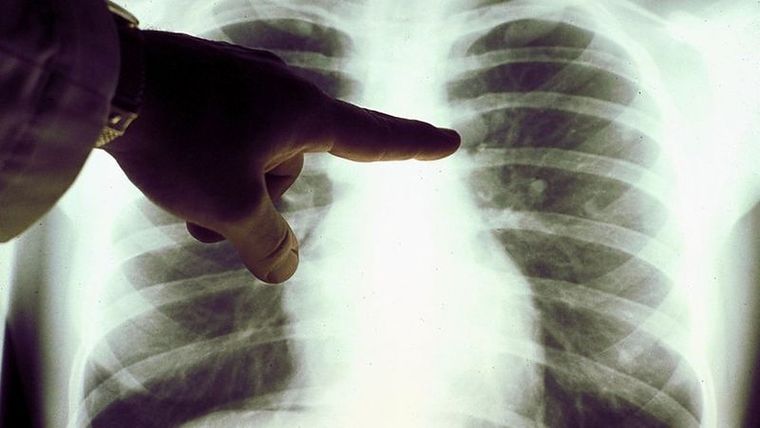

Se le diagnostica un linfoma de Hodgkin clásico en estadio III (el linfoma afecta a áreas ganglionares localizadas a ambos lados del diafragma o por encima del diafragma y en el bazo).

Poco después del diagnóstico, ingresó con dificultad para respirar y se le diagnosticó neumonía por SARS-CoV-2 [covid-19] positivo por PCR.

Cuatro meses después, la inflamación de los ganglios se había reducido y una exploración PET reveló una remisión generalizada del linfoma.